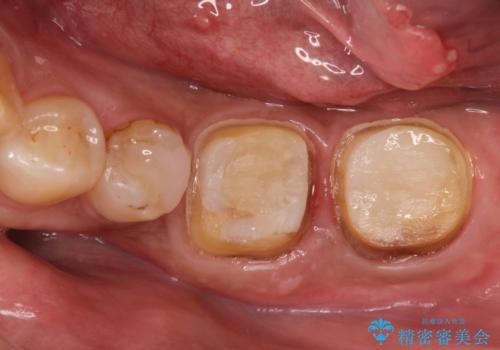

- 他院で治療したが、痛みが続いていることを主訴に来院されました。

痛みの原因歯を特定し、根管治療を行い、オールセラミッククラウンにて咬合回復しております。

根管治療は林先生に依頼しております。